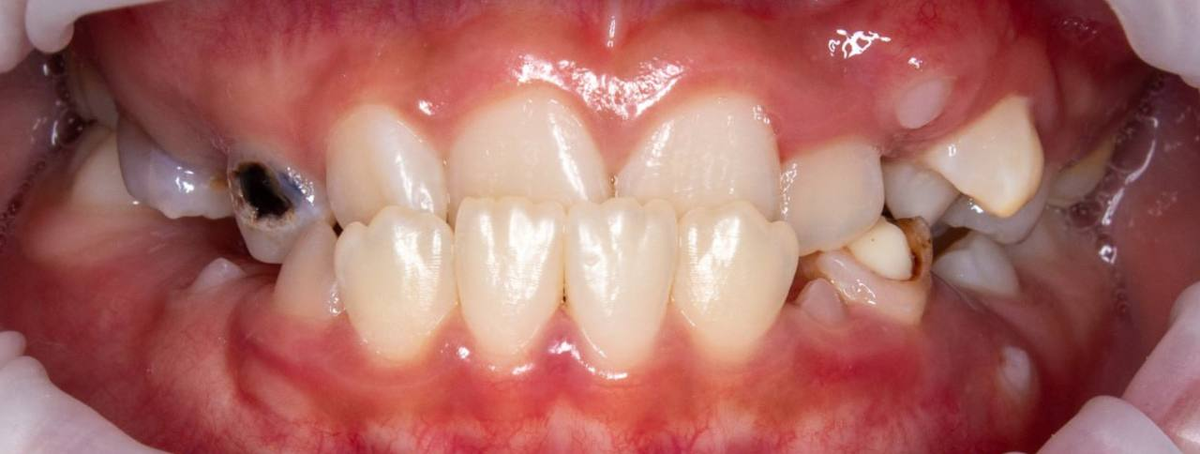

Через 7 месяцев после завершения:

— результат стабилен,

— дыхание и жевание нормализовались,

— изменился овал лица,

— лицо гармонизировалось,

— девочка снова улыбается.

И посмотрите, какие красивые у пациентки свои зубы после коррекции прикуса!